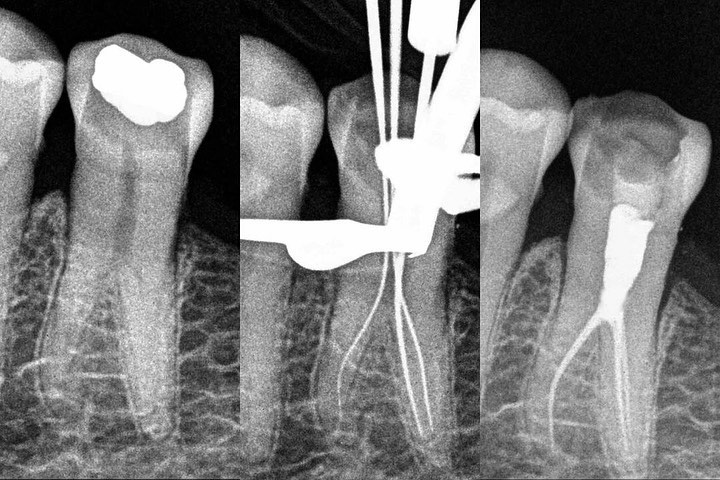

By• @nikhilmodiendodontics Back breaker of the week! 2.5 hour single visit endo. This was my third lower premolar with unusual anatomy this week. Need to have a word with Santa about the kind of teeth he’s giving me to treat this Christmas 🤕.

Almost a taurodont this one. Let’s hope I have enough justice to this shape and this tooth lasts for a long time🤟🏼